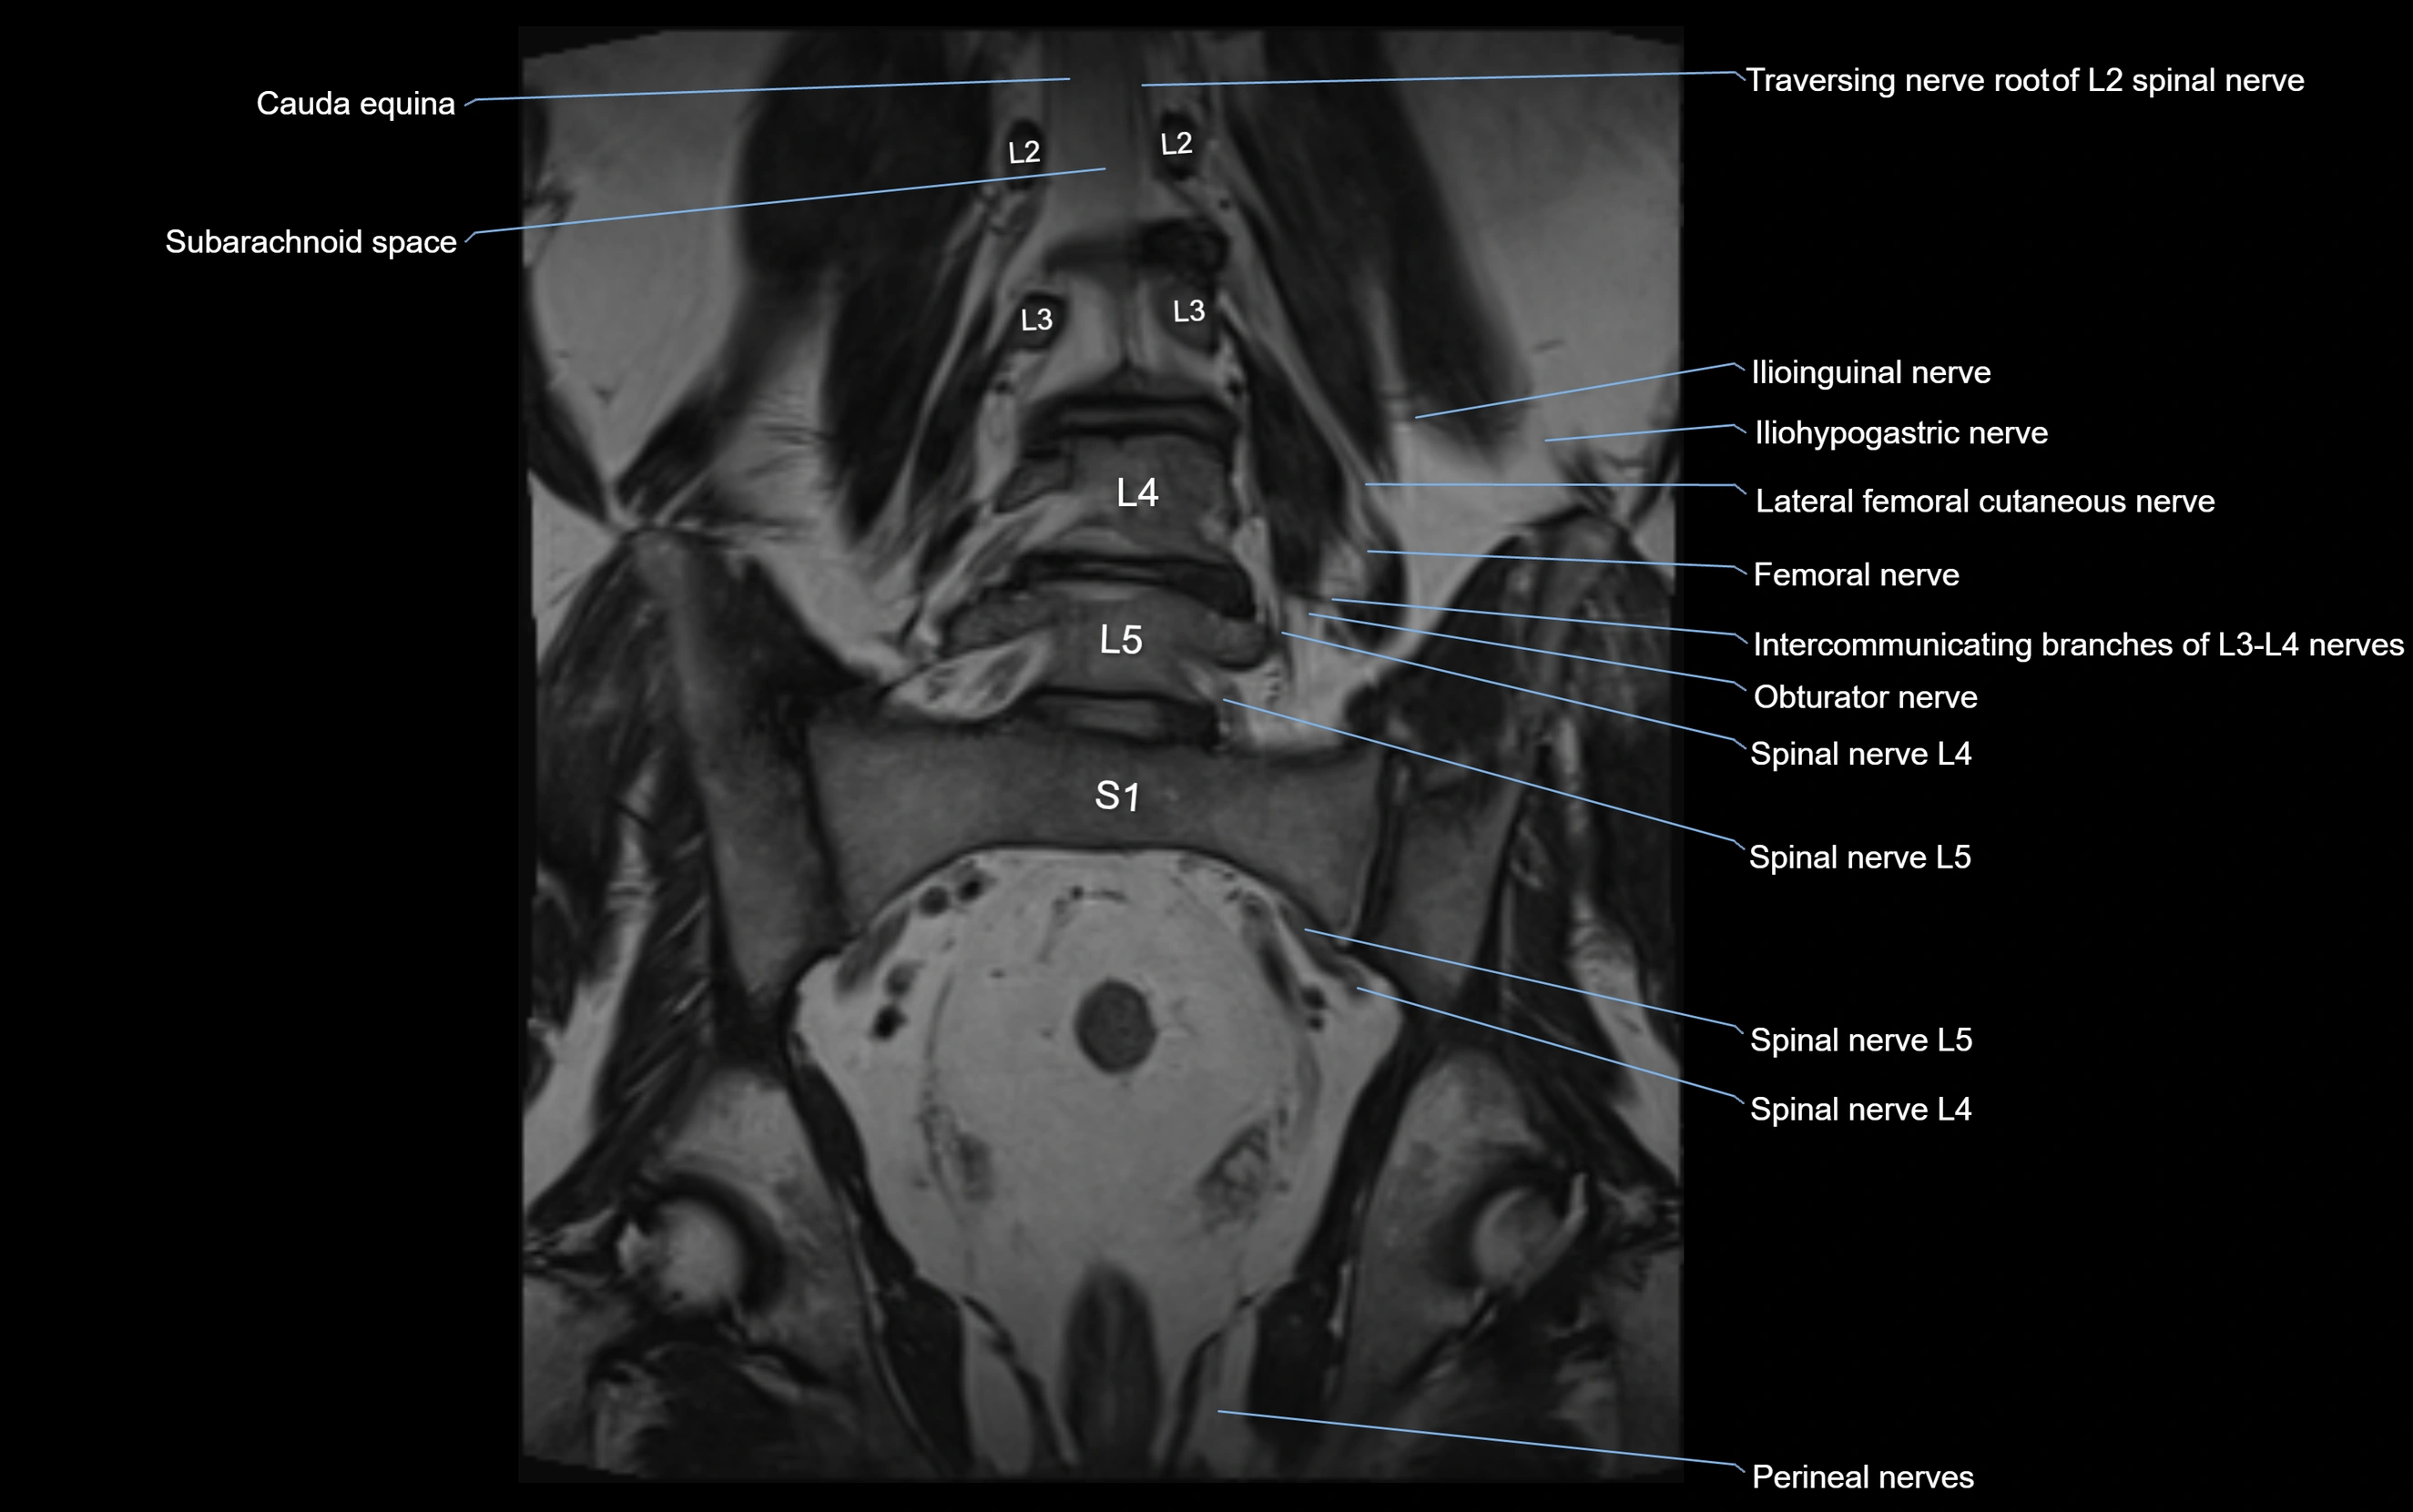

MRI image

image